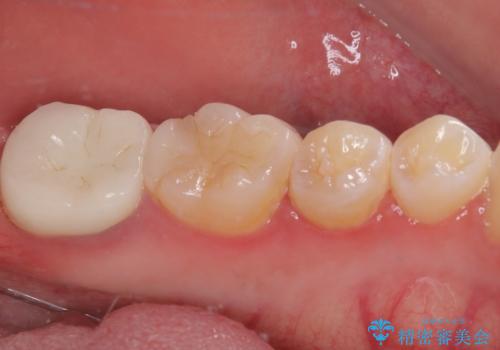

根管治療後は状態を確認し、オールセラミッククラウンにて補綴治療を行うこととしました。

歯根先端付近の歯槽骨が溶けてるレントゲン像が認められましたが、治療から半年後のレントゲン写真では、消退している様子が認められました。